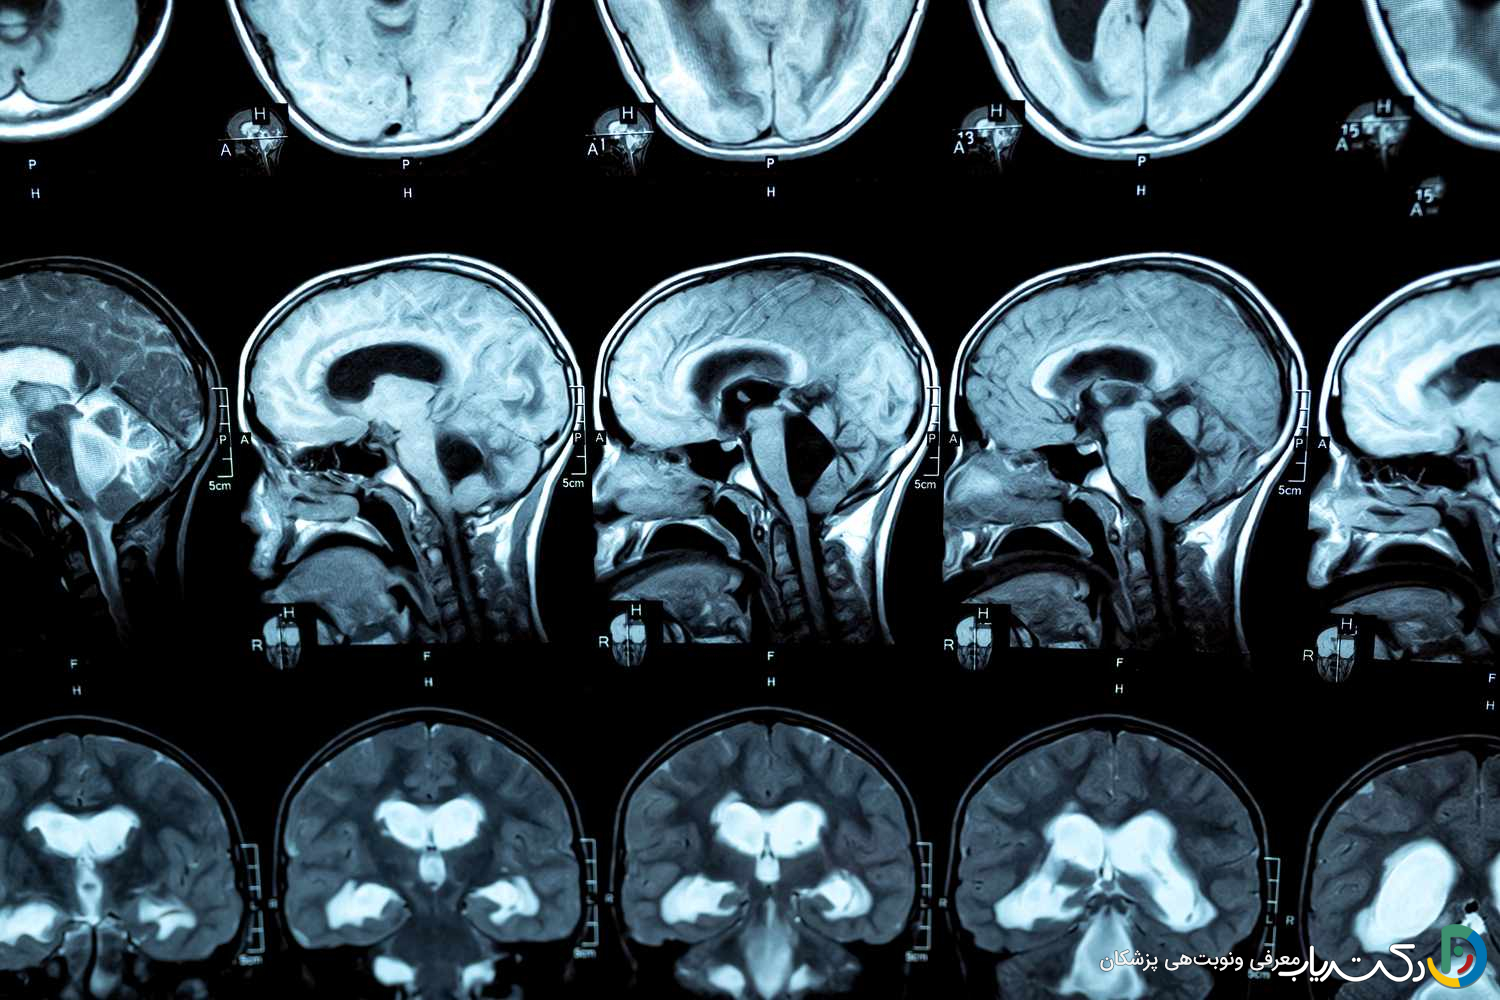

- تشخیص قطعی: تشخیص دقیق یک فرآیند چندمرحلهای است که با معاینه کامل عصبی آغاز شده و با روشهای تصویربرداری پیشرفته مغز مانند MRI (استاندارد طلایی برای مشاهده جزئیات) و CT اسکن (برای ارزیابی سریع و اورژانسی) تأیید میشود.

- تصویربرداری رزونانس مغناطیسی (MRI): امآرآی بهعنوان استاندارد طلایی برای تشخیص و ارزیابی کامل هیدروسفالی شناخته میشود. این روش بدون استفاده از اشعه ایکس، با استفاده از امواج رادیویی و یک میدان مغناطیسی قوی، تصاویر بسیار دقیق و با جزئیات بالا از ساختارهای نرم مغز ایجاد میکند. MRI نه تنها بزرگ شدن بطنها را با دقت فوقالعاده نشان میدهد، بلکه میتواند علت زمینهای مانند تومور، کیست، التهاب یا ناهنجاریهای ساختاری را نیز شناسایی کند. سکانسهای خاصی از MRI (مانند CINE-MRI) حتی میتوانند جریان و سرعت حرکت CSF را در مغز به تصویر بکشند و به تشخیص نوع انسدادی از ارتباطی کمک کنند.